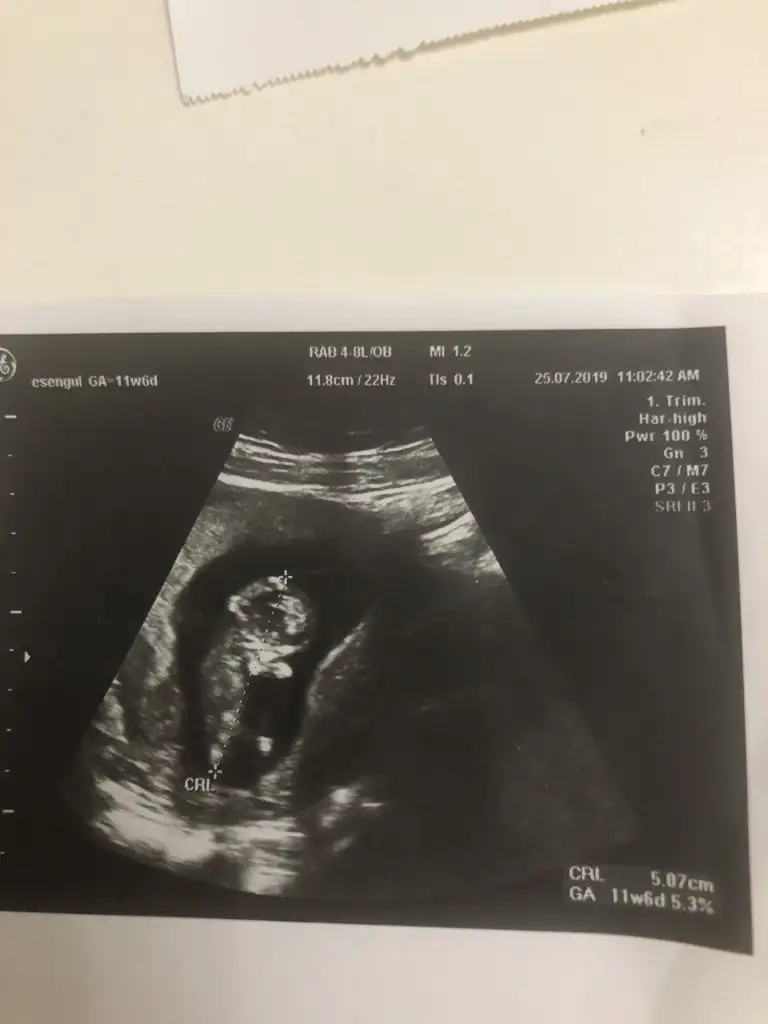

Bunlarda az önce alınan resimler normalde 11 hafta 6 günlük ama usg de 12 hafta 6 günlük

Kızlaar bende çok merak ediyorum geçen hafta 11+5 ken bunlar İpucu veriyormu sizce cinsiyet nedir?

Siz erkek istiyordunuz galiba.nub çizgisine ve kafa yapısına göre yorum yapıyorum.cinsiyet oluşmadan önce nub çizgisi oluşur.bu çizgi paralelse kız,dik ise erkek demektir.sizin bebeğinizin nub çizgisi bariz paralel.kafa yapısı da oval.erkeklerin kafa yapısı daha yuvarlak olur. Doktor kesin erkek dedi mi size? Buda cinsel organı diye gösterdi mi? Kaç haftalıksınız şuan?Doktor organını bile gösterdi bu çıkıntı olabilir diye yine de cevabınız için teşekkür ederim merakımdan soruyorum yanlış anlamayın neye göre Tahminde bulunuyorsunuz mesela son resim tam olarak neyi gösteriyor hiçbirşey anlamadım

Evet gönlümden geçen erkek Bi tane kızım var çok ta sevinmiştim siz şimdi kesin kız deyince moralim bozuldu biraz. Şu an sat a göre 11 hafta 6 gün usg ye göre 12 hafta 6 gün. Doktor erkeğe çok benziyor çıkıntısı burada diyerek gösterdi kesin erkek demedi yüzde 80 erkek dedi ama bazen kızlarda da bu çıkıntı oluyor dedi. Hatta bu Nub teorisinden de bahsettim belli olmaz bazen dik bazen paralel bile olabilir dediSiz erkek istiyordunuz galiba.nub çizgisine ve kafa yapısına göre yorum yapıyorum.cinsiyet oluşmadan önce nub çizgisi oluşur.bu çizgi paralelse kız,dik ise erkek demektir.sizin bebeğinizin nub çizgisi bariz paralel.kafa yapısı da oval.erkeklerin kafa yapısı daha yuvarlak olur. Doktor kesin erkek dedi mi size? Buda cinsel organı diye gösterdi mi? Kaç haftalıksınız şuan?

Kızlarda da bu çıkıntı oluyor dediyse nub çizgisinden bahsediyor.11 12 haftada cinsel organ tam anlamıyla oluşmuyor nub çizgisi oluyor.13 14 haftalarda organ oluşmuş oluyor.yani direkt olarak pipi göstermemiş.bilmiyorum doktor erkek dediyse erkek olabilir.ben bariz kız görüyorum bu usg de.elbette doktorlar daha iyi bilir tabi.rabbim gönlünüzdekileri nasip etsin inşallah.siz sorduğunuz için cevapladım.ama bana göre bu bebiş kızEvet gönlümden geçen erkek Bi tane kızım var çok ta sevinmiştim siz şimdi kesin kız deyince moralim bozuldu biraz. Şu an sat a göre 11 hafta 6 gün usg ye göre 12 hafta 6 gün. Doktor erkeğe çok benziyor çıkıntısı burada diyerek gösterdi kesin erkek demedi yüzde 80 erkek dedi ama bazen kızlarda da bu çıkıntı oluyor dedi. Hatta bu Nub teorisinden de bahsettim belli olmaz bazen dik bazen paralel bile olabilir dedi